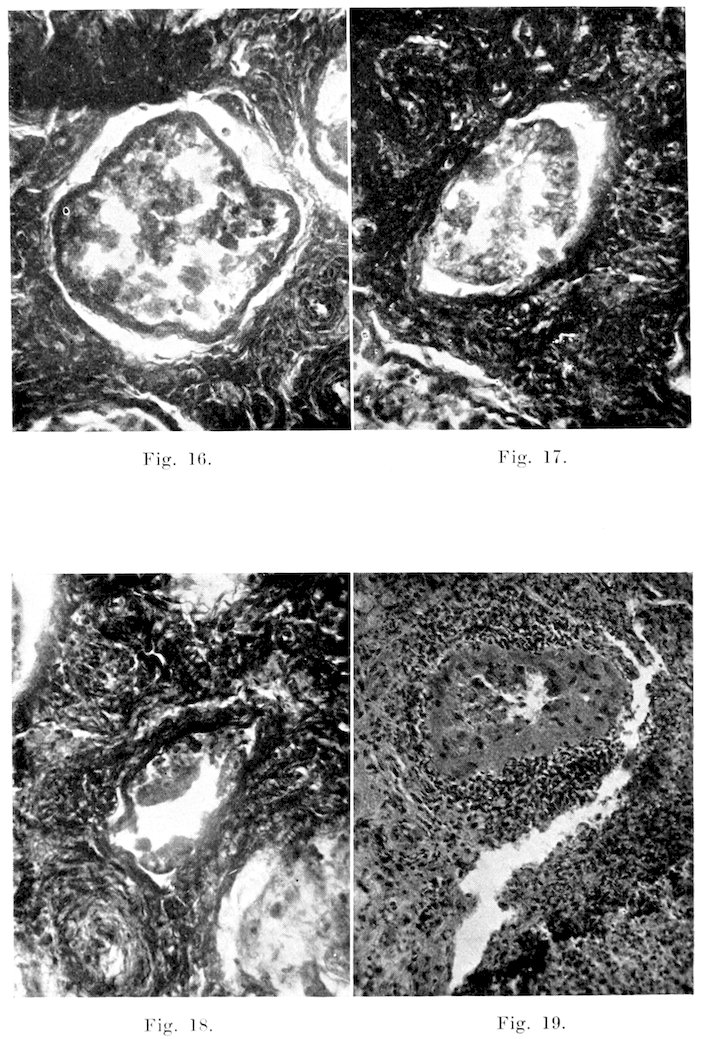

Microscopically, changes are quite common and varied in character. In the seminiferous tubules, the changes range from a slight desquamation of the germinal epithelium to atrophy and complete degeneration of the entire tubule, as was the case in the left testis of Bull 1. In the mild cases, spermatogenesis occurs apparently in a normal manner up to the spermatid stage, at which point many of the cells degenerate and slough off. These appear in the seminal fluid, associated with the few sperms that reach maturity. This sloughing and degeneration may be localized in a few of the tubules, or it may be widespread over the entire organ. Likewise, the changes may involve not only the more mature cells, but they may be so severe as to cause almost total degeneration and desquamation of the seminal epithelium, as in Fig. 15. These defects in spermatogenesis are of course evidenced in the semen by the presence of immature, or abnormal types of sperms. With cessation of spermatogenesis or degeneration of the epithelium of the entire gland, no sperms are formed. Not infrequently one finds numerous tubules, or even the entire testis in which the germinal epithelium is intact, but there is little or no evidence of mitosis, as in some tubules of Bull 6. The cells are several layers deep as in the normal condition, but they are not dividing. This condition is shown in Fig. 13.

27In the more chronic forms, the tubules become atrophied, and frequently disappear entirely. The membrana propria may become thickened, due to excessive connective tissue formation, or infiltration with serum or exudate. On the other hand, a distinct atrophy may occur. The stroma of the organ not infrequently is thickened by inflammatory exudates, or by a noticeable increase in the connective tissue. In some testes, the connective tissue is so much increased that the tubules rapidly become atrophied, and disappear. In abscess formation, due to acute inflammations, the entire organ becomes enlarged, markedly hyperaemic, and infiltrated with leucocytes. Necrotic areas appear here and there in the parenchyma. The rete often shows a marked degeneration of the lining epithelium, and atrophy caused by increase of the interstitial connective tissue.

Epididymis: This organ not infrequently presents gross abnormalities, and very often is pathological on microscopic examination. Acute, inflammation, with induration or abscess formation, is very common in the tail, but less so in the head and body. Possibly this is caused by the fact that the tail is the most pendant portion of the organ. In these cases, the tail is enlarged, soft, and quite hot and painful on physical examination. Enlargement, due to a connective tissue induration, occurs occasionally in all three parts, and the inflammation may produce adhesions to the adjacent serous membranes. Inflammation of both the parietal and visceral layers of the tunica vaginalis is very common. In those cases, the membrane usually is quite hyperaemic, and on the surface it presents many small reddened tufts of newly-formed connective tissue. In adult bulls it is exceptional not to find at least slight evidence of some previous inflammation. In all of the numerous bulls examined, both apparently normal and sterile, I have found but one in which some evidence of inflammation (either present or past) could not be found. Along with the fibrous tufts, are numerous fine strands of connective tissues passing from the covering of the tail of the epididymis to the adjacent portion of the parietal layer of the tunica. The strands often extend even to the upper part of the head.

Microscopically, inflammation of the part is shown by hyperaemia, loss of cilia of the lining cells, and exudation. In the more severe forms, the lining cells which furnish considerable secretion for the nourishment and stimulation of the sperms, become degenerated, and are exfoliated into the lumen, as in Fig. 21. This condition is very common in sterile bulls, and those of lowered fertility. In the chronic types, the interstitial connective tissue is increased in amount, leading to degeneration and atrophy of part or all of the tubules, as in the case of Bull 2. Infiltration with leucocytes, and necrosis, are the predominating lesions in the pyogenic types of inflammation.